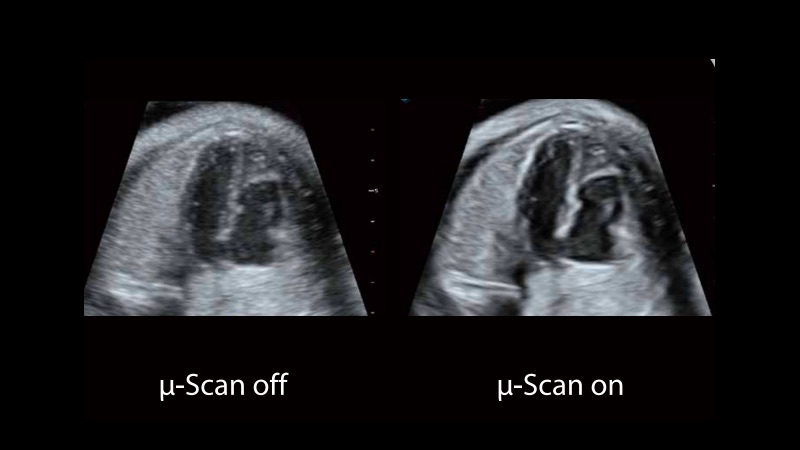

μ-Scan

The new generation μ-Scan imaging technology greatly improves the visibility of organs and lesions. The high-definition contrast resolution will suppress speckle artifacts while maintaining real tissue architecture.